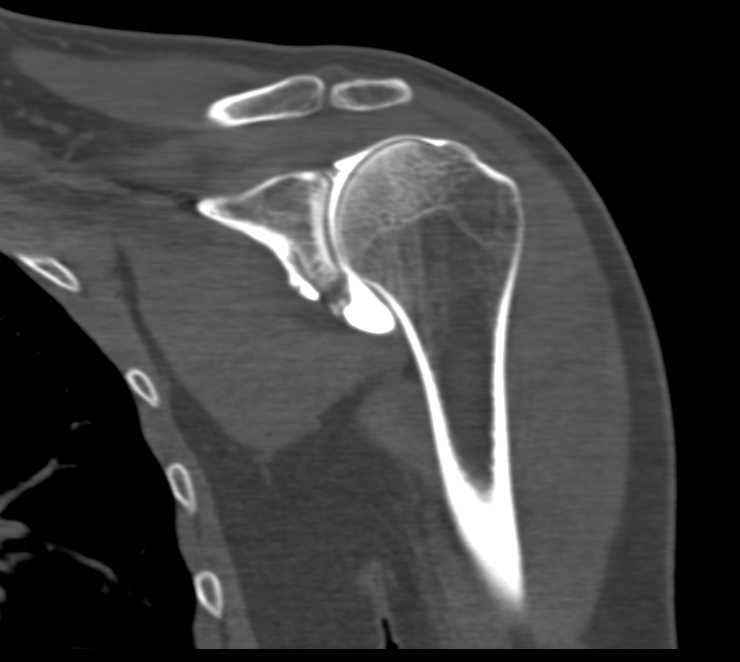

Diagnosis

Metastatic Neuroendocrine Tumor to the Liver and Spine